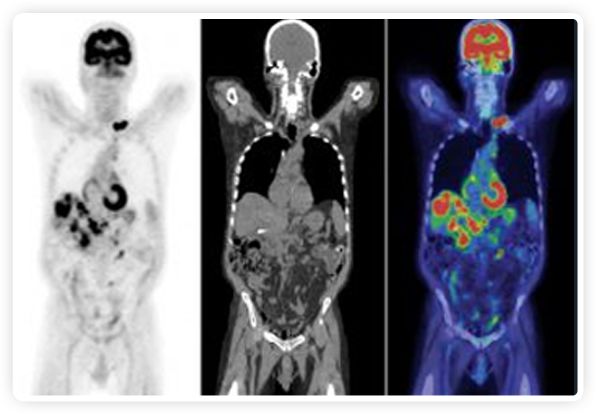

正電子發(fā)射斷層掃描(PET)是癌癥檢測(cè)中已建立的成像標(biāo)準(zhǔn),與其他成像方式相比,PET能提供高靈敏度和特異性的圖像。

到目前為止,放射腫瘤學(xué)中(使用的圖像主要是結(jié)構(gòu)性的,而PET圖像可以提供生物學(xué)信息。通過使用注射示蹤劑,例如18-FDG,PET可以描繪腫瘤的代謝活性,使其“點(diǎn)亮”。(FDG是用于可視化癌癥代謝的最廣泛使用的示蹤劑。與正常組織相比,腫瘤細(xì)胞保留更高水平的FDG。)不同的PET示蹤劑可以識(shí)別腫瘤的不同生物學(xué)特征,例如特定生物標(biāo)志物抗原(例如,PSMA)或甚至探測(cè)免疫系統(tǒng)本身(例如,PDL1表達(dá)或活化的T細(xì)胞)。